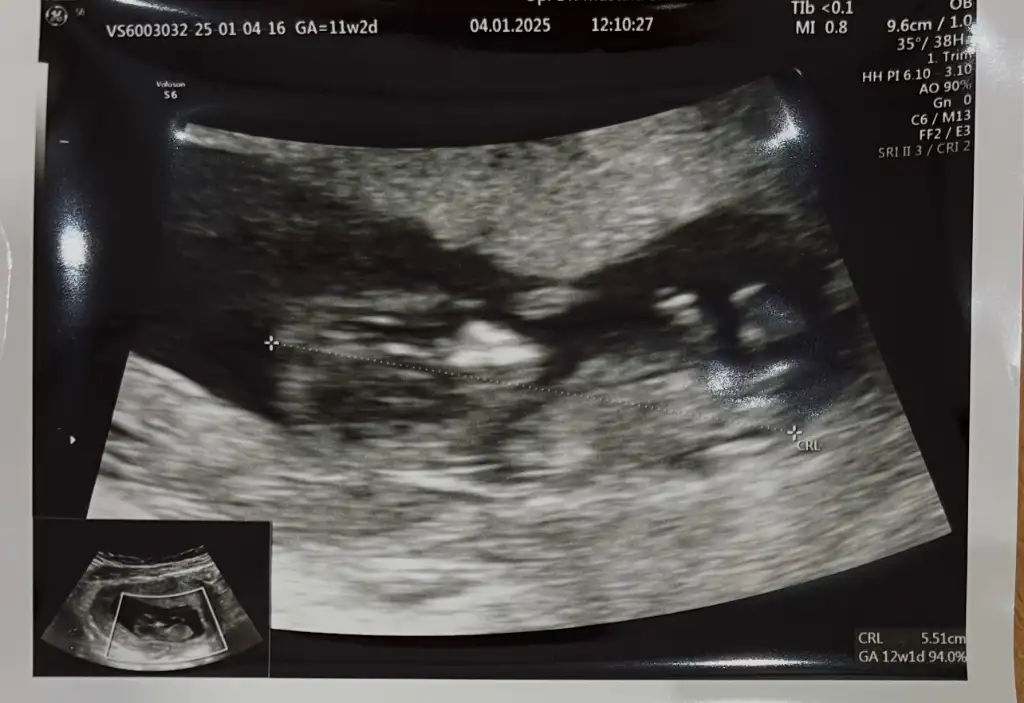

Merhaba benim ultrasona da bakarmısınız rica etsem karın dan baktığında solumda hep kese

Eklentiler

• IMG-20250103-WA0004.webp

IMG-20250103-WA0004.webp

29,9 KB · Görüntüleme: 47

Bence erkek mezhanesi yukarda . Hayırlı evlat olsun